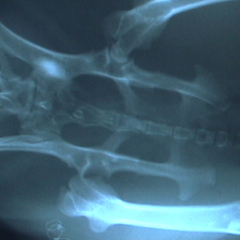

大腿骨頭切除術を施したうさぎ

骨は正常な位置にあり周りの太い筋肉によって、足はしっかり支えられる。通常1週間で足を使えるようになる。 |